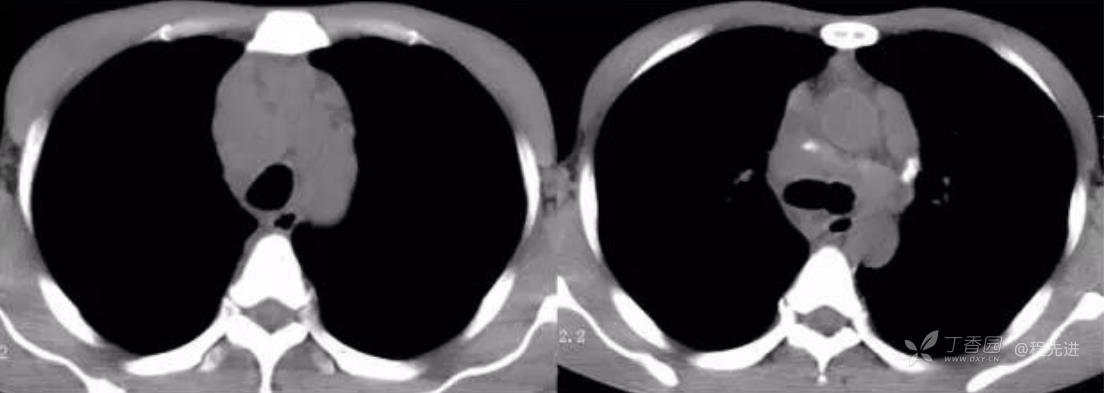

动脉期

动脉期CT值32HU,静脉期CT值54HU